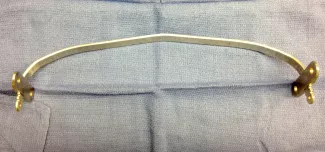

Open repair, called the Ravitch procedure, is done through a horizontal incision across the mid chest. In this repair the abnormal costal cartilages are removed, preserving the lining of cartilage, thus allowing the sternum to move forward in a more normal position. This procedure takes approximately 4–6 hours. In certain patients, an osteotomy (a break) in the sternum is done to allow the sternum to be positioned forward. In addition, to keep the sternum elevated in the desired position after the removal of the cartilages and the osteotomy, a temporary metal chest strut (bar) may need to be placed.

Repair with a metal pectus bar, called the Nuss Procedure, is achieved by bending a stainless bar to fit the chest wall. The bar is then inserted and secured through a small incision under each arm using the aid of a endoscope to monitor and avoid injury to the heart during insertion. The bar goes over the ribs and under the sternum, to push the sternum forward into the new position. The ends of the bar are secured to the chest wall. This procedure takes between 1–2 hours.